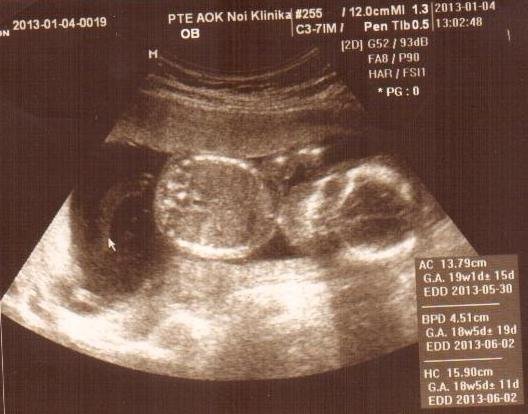

És ha már ismét a szülésnél tartunk, a héten következett a következő genetikai ultrahang. Nagy többségnek itt kiderül a baba neme, ezért nagy izgalommal indulunk neki a napnak. 11:40re van időpontunk a szülészeti klinikára. Arra a csodálatosra, ahol a múltkor is voltunk. 😉 Mivel akkor, pár perccel az érkezés után egyből behívtak, mertem feltételezni, hogy ez most is így lesz. Mikor megérkeztünk, annyian voltak, hogy a váróba sem fértek el, így minden reményem elillant a gyors bejutást illetően. Nem baj, türelmesen vártunk. Egy laza 2 órát…. Közben megismerkedtem egy csajszival, azt hiszem Timinek hívják, aki napra pontosan annyi idős terhes, mint én. És vicces, mert minden nap ugyanakkor jött ultrahangra, mint én, és az orvosnál is mindig összetalálkoztunk. 🙂 Most hogy így ennyi időnk volt, ráértünk beszélgetni. Kiderült, hogy bajai, így ő sem az a lány, akivel együtt tudok kismama tornára járni, vagy nyáron babakocsit tologatni… 🙁 Pedig aranyos. Könyvelőként dolgozik, ez még jól jöhet bármikor! 🙂 Ami rettenetesen felbosszantott, hogy benéztem a váróba, és tele volt cigánnyal. (igen cigánnyal, leírom, mert ez a saját blogom, ide azt írok, amit akarok!) Brutál büdös, és egy terhes cigány asszonyhoz tartozott egy egész pereputty. Apa, anya, gyereke… stb. Totál kibuktam rajta, hogy bent ülnek, mi meg pocakosok, kint állunk, mert bent nincs hely. És nekem még nincs is akkora hasam, de aki 7-8 hónaposan ott ácsorgott, mert a „kedves” benti embereknek eszükbe sem jutott átadni a helyet… Természetesen az én hős férjem felajánlotta hogy szívesen szóvá teszi ezt odabent nekik 🙂 De nem, nem balhézunk, türelmesen várunk. Még a váróban megtudtuk, hogy a doktor úr, aki a mai ultrahangot végzi, nem mondja meg soha senkinek a baba nemét, mert ő nem szeret találgatni. Na, szuper!!! Mikor sorra kerültünk, rögtön így indítottam neki, hogy tudom, hogy nem szeret jósolgatni, deeeee ha látja, hogy kukija vagy van nunija, mi kíváncsiak vagyunk rá. De természetesen nem mondott semmit. Szerencsére minden rendben van, egészséges, minden adat megfelelő, amit mértek, és mindene megvan. Persze kértünk képet, de utólag már lehet, hogy úgy gondolom, hogy nem kellett volna. Az egész gyerek egy nagy has. Nem csoda, ha nem látszik, milye van…. Teljesen készen vagyok ettől a képtől.

Remélem ez csak egy rosszul sikerült felvétel, és a gyerekem nem csak egy nagy has!!!! Ha valaki esetleg nem tudná kivenni a képből, a jobb oldali gömb a feje, a bal oldali a hasa! Se keze, se lába!!!! (a képen! igaziból van! Csak itt nem látszik.)

Vagy lehet, hogy a doktor úr direkt csinált ilyen előnytelen képet, mert kiakasztottam azzal, hogy egyből betaláltam a baba nemével. Elég nyers volt a dokibácsi stílusa, amolyan Doktor House-os. Igaziból én bírom az ilyen stílusú embereket, csak sokan kikészülnek ettől a típustól. Egy szónak is száz a vége, még mindig nem tudjuk, fiú, vagy lány?!?!?